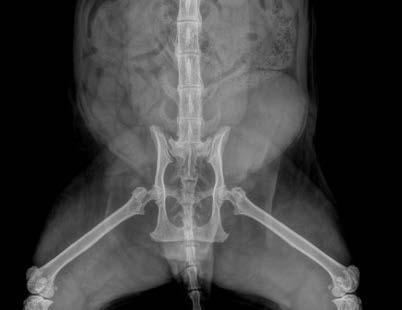

Opal has diffuse idiopathic skeletal hyperostosis (DISH). This can cause limited spinal range of motion, nerve impingement leading to spinal pain and pain on the legs. The nerve impingement can also cause muscle weakness, paresis, and changes in spinal reflexes.

Opal was diagnosed with diffuse idiopathic skeletal hyperostosis (DISH) after discussion with Dr Richard Malik, as I had never actually seen a case like this before.

DISH is a systemic non-inflammatory disorder of the axial and peripheral skeleton that has also been described in humans and dogs.

DISH results in the ossification of soft tissues including spinal ventral longitudinal ligaments and sites of attachment of tendons and capsules to bone. In dogs and humans the prevalence increases with age.

Clearly—the skeletal changes in this cat ARE SEVERE. There is every possibility that there is intervertebral disc protrusion adding to the cat’s disability by compressing the spinal cord or nerve roots exiting intervertebral foramina. The only way to determine this is by advanced imaging, CT, a CT myelogram, or an MRI scan (ideally all three!). The problem of course is we do not know what causes DISH in cats or dogs, and we cannot treat the underlying problem, so even if there is a discrete surgical lesion—can we be sure fixing it will help the cat? And the imaging would likely cost $5,000 and surgery might cost another 5-10 thousand dollars. A lot of money to pay with an uncertain prognosis.

Figure 1. Lateral radiograph showing diffuse idiopathic skeletal hyperostosis (DISH)

Figure 2. Dorsoventral forelimb and cervical spine Figure 3. Lateral thoracic spine Figure 4. Ventrodorsal hips

Figure 5. Ventrodorsal cervical, thoracic and lumbar spine